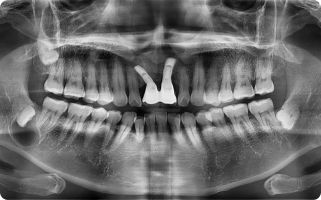

난이도 높은 사랑니 발치도, 정밀 CT 진단과 숙련된 수술 경험으로

대학병원 의뢰 없이 한 공간에서 바로 진행합니다.

구강 검진, 촉진, 교합 검사 또는 파노라마, CBCT, MRI 촬영을 통해

눈에 보이지 않는 부위까지 선명하게 관절 및 디스크 상태를 확인합니다.

정밀 진단

- 구강 검진, 촉진, 교합 검사

- 필요 시 파노라마, CBCT, MRI 촬영을 통해 관절 및 디스크 상태 확인